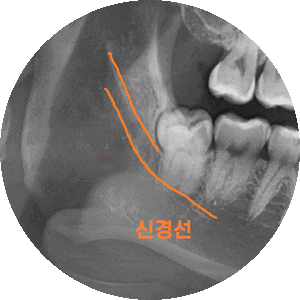

이렇게 누워있는 사랑니는 딱봐도 뽑기 어렵게 생겼죠?

그냥 잡고 뽑으면 방향이 가로라

나올 수가 없어요~

이런 치아는 쪼개서 조각을 내어 뽑아줘야합니다.

시간이 많이 걸리겠죠~?

매복 사랑니의 경우 신경관과 근접한 경우가 많아

ct까지 같이 찍게 되는데요~